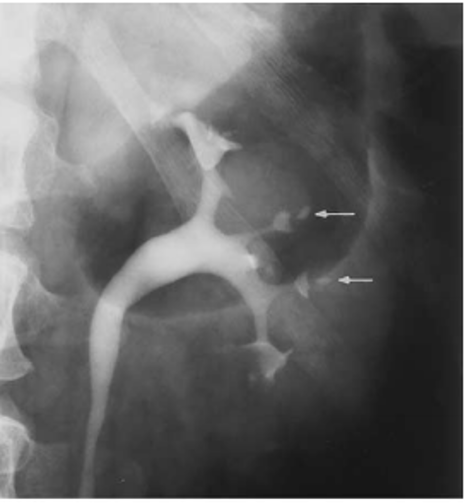

multiple ureteral outpouchings that are smaller than 5 mm

most common location of ureteral pseudodiverticulosis

bilateral, upper 2/3 of ureter